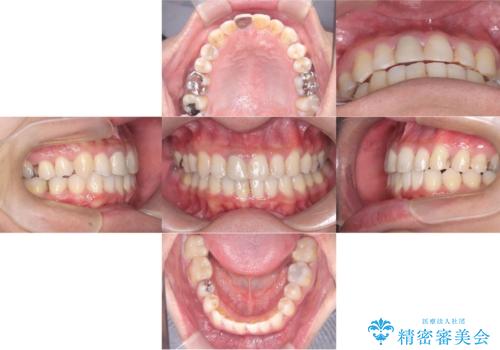

- 30代男性

- 1年9ヶ月

- 10-30回

- 「八重歯と歯のでこぼこを治したい」を主訴に来院された患者様です。

歯は抜かずに奥歯の遠心移動とIPRで八重歯とでこぼこを改善しました。

インビザラインはご飯と歯ブラシ以外はマウスピースをつける矯正です。

使用時間をきちっと守っていただければ、歯のでこぼこなど綺麗に治すことが出来ます。